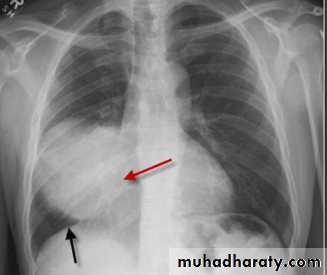

Silhouette sign: invaluable sign for localizing dis. From plain CXR.

Intrathoracic lesion touching heart, aorta or diaph. Obliterate their bordersIt has two important applications:

1- localize shadow by observing which border is obliterated, e.g.: loss of heart border means the shadow in ant. Half of the chest, loss of diaph. Outline indicate the dis. Of pl. or in lower lobes.

2- it makes possible on occasions to dx. Disorders as consolidation or collapse even when its presence is uncertain, when it is in contact with med. Or diaph., losing their sharp outlines.

Rt. Ant. Med. Mass silhouette rt. Cardiac border

Pneumonia, with air bronchogram, partly ill defined, silhouette positive